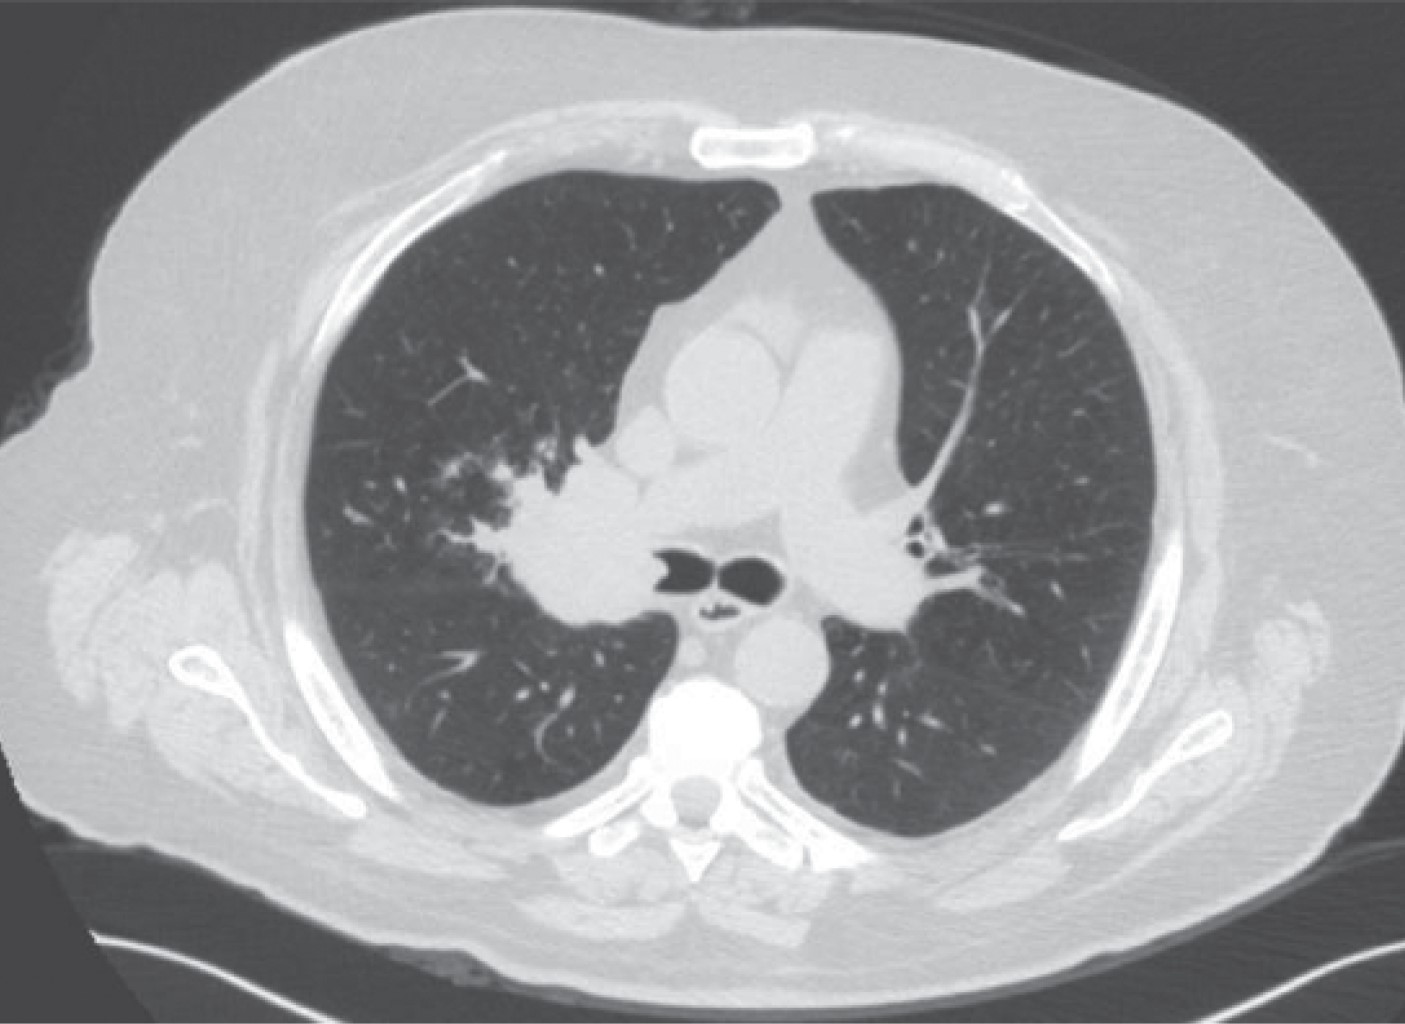

The appearance of a multiple primary malignant neoplasms is more frequent in elderly patients, lung cancer is the leading cause of cancer death worldwide, the frequency of synchronous and metachronous lung cancers has increased in recent years due to advances in early detection techniques, multiple malignancies can be classified as synchronous or metachronous according to the time of onset in relation to the first malignancie, synchronous those that appear in the first six months and metachronous as those that appear after six months. We present the case of a 66-year-old male patient with a history of right radical nephrectomy for clear cell renal cancer, who goes to the emergency department seven years later for respiratory symptoms and hemoptysis. In his study protocol, he is diagnosed with a parahiliary right upper lobe endobronchial tumor of epidermoid lineage involving the right bronchus.

Figure 3